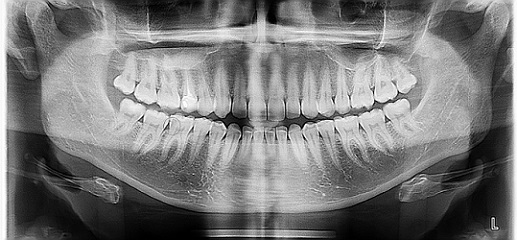

a) panoramatický přehledný snímek chrupu (OPG ortopantomogram neboli panoramatický snímek zubů) - u nových pacientů bývá zhotovován téměř paušálně. Slouží ke zjištění stavu kosti v okolí zdravých a endodonticky léčených zubů (devitálních - mrtvých zubů, jejichž kořeny jsou ošetřeny kořenovou výplní), vidíme její úroveň (kam až kost okolo zubu sahá) při diagnostice možné parodontózy, přítomnost a uložení zubů moudrosti, jiné patologie – nemoci zubů … Jak už název napovídá, pomůže nám udělat si přehled o stavu zubů a kosti v dutině ústní.

Foto 1-2: Pořízení panoramatického snímku chrupu u pacientky.